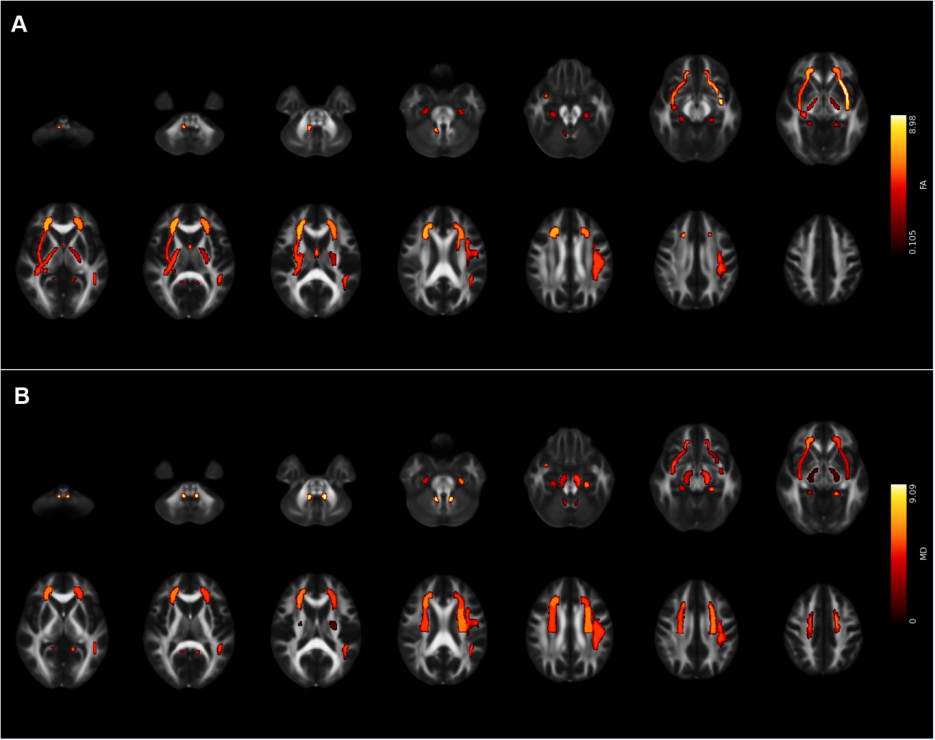

研究团队招募了49名4-12岁的孤独症儿童,实验组进行了为期12周以小篮球形式为主的团体互动型运动技能学习,对照组则接受常规护理。本研究除了采用自行研发的适用于孤独症儿童共同注意任务外,还采用了眼动追踪技术和磁共振扫描手段,对所有被试进行了基线水平和12周后的数据采集。结果发现,实验组儿童在经过运动干预后,共同注意显著提高,线索首次注视时间也到了显著改善;同时,上纵束、额枕束、扣带、钩状束等联络纤维以及放射冠、内囊、外囊、大脑脚等投射纤维完整性显著增强。

图1. 干预后,在FA (A)和MD (B)存在显著交互作用的白质区域

此外,研究结果发现,实验组儿童所发现的减少的首次注视时间与降低的左侧上放射冠和左侧上额枕束平均弥散率呈显著正相关。这表明,篮球运动技能干预有效改善了孤独症儿童的共同注意力,其改善机制可能与感觉感知、空间和早期注意功能相关的白质纤维完整性变化有关。